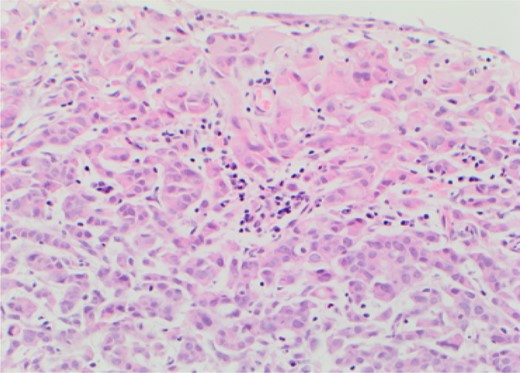

Rigid cystoscopy identified bullous oedema surrounding the 4–5 cm solid tumour that covered the entire bladder base. It had typical endoscopic appearance of a transitional cell carcinoma (TCC). Only after complete resection were the ureteric orifices identified with both showing good signs of peristalsis and efflux negating the need for stenting. Loop biopsies were taken to completely resect the satellite lesions on the right wall which had appearances atypical of a TCC and tissue was sent separately for histological diagnosis (Fig. 2). A 22 Fr catheter remained in situ until post-operative renal function stabilized and the patient was discharged awaiting histological diagnosis.

Metastatic lobular carcinoma of the breast identified on right wall of bladder.

The histopathological analysis identified two distinct malignant entities. The solid tumour at the base of bladder was confirmed as muscle invasive bladder cancer (G3pT2) whilst the satellite lesion showed features suggestive of metastatic lobular carcinoma of the breast. Following discussion at both urological and breast MDTs palliative chemotherapy was administered to address the metastatic breast cancer whilst palliative radiotherapy was used to contain the primary bladder cancer.